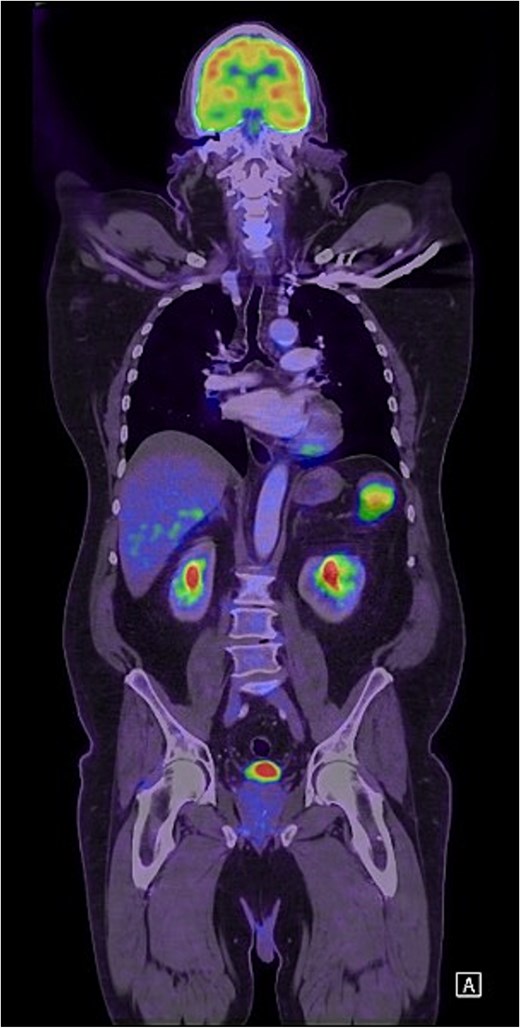

Unfortunately, 6 months later he was diagnosed with locally advanced squamous cell carcinoma of the face and was subsequently commenced on immunotherapy. As part of the work-up, he was re-staged with a positron emission tomography (PET) scan which found an isolated PET-avid soft tissue lesion in the LUQ measuring 51 × 37 mm in size (Fig. 3) for which he was clinically asymptomatic. Following multidisciplinary discussion, he underwent a laparoscopic soft-tissue resection with intraoperative findings of a mobile, soft tissue lesion located in the LUQ. Histology demonstrated foreign body granulomatous inflammation to cholesterol clefts in keeping with a CG. He had an uneventful postoperative recovery and remained asymptomatic on review in the surgical outpatient clinic.

Coronal FDG PET scan of the head, neck, chest, and abdomen demonstrating a PET-avid LUQ lesion.